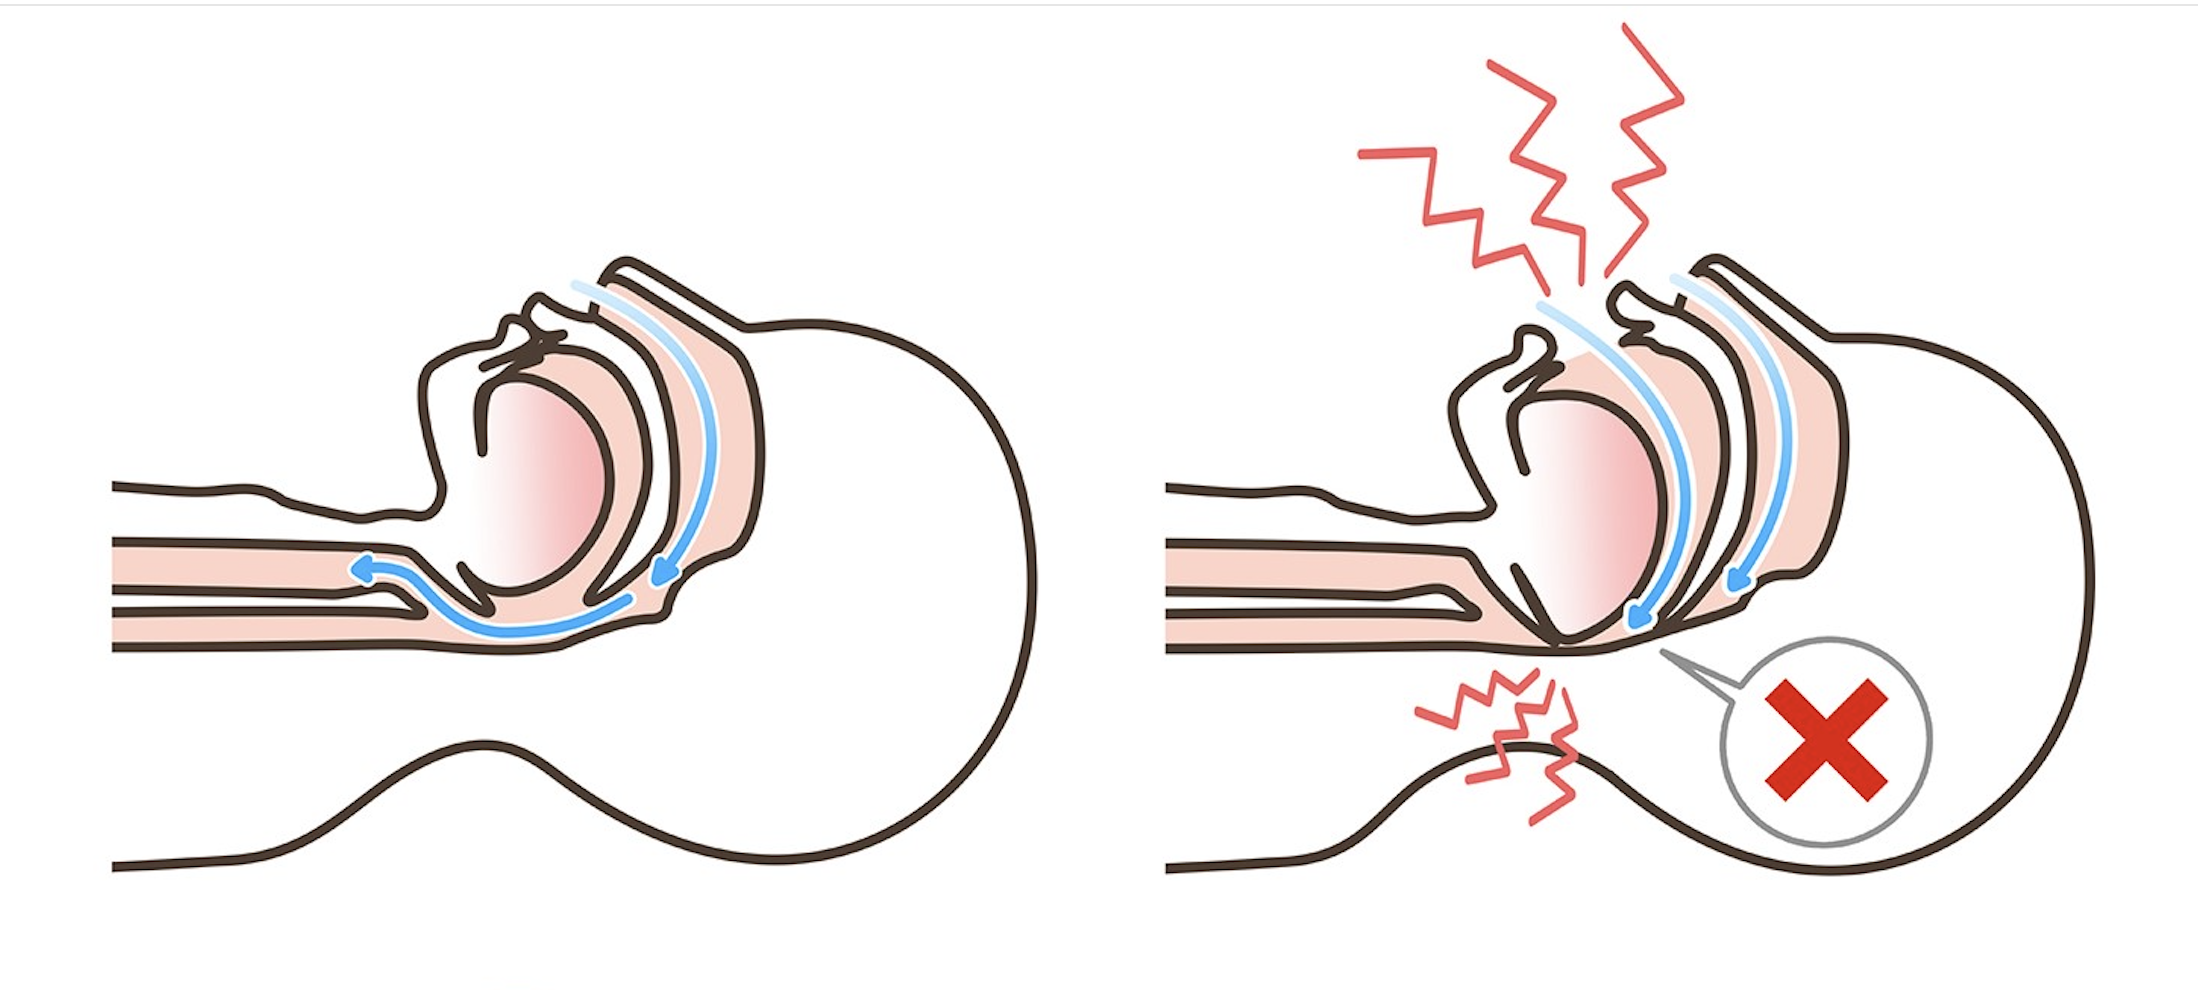

私たちは呼吸をする時、鼻や口から空気を取り込み、喉の奥(気道)を通って肺へと送ります。

正常な状態であれば、気道は十分に確保され、スムーズに空気が流れます。

しかし、睡眠中は全身の筋肉がリラックスするため、舌や喉の周りの筋肉も緩んで下がります。

仰向けで寝ると、重力によって舌根(舌の付け根)や軟口蓋(喉の奥の柔らかい部分)が沈み込み、気道を狭くしてしまいます。

狭くなった気道を空気が通る時に、粘膜が振動して出る音が「いびき」です。

そして、気道が完全に塞がれてしまうと「無呼吸」になります。

Er:YAG(エルビウムヤグ)レーザーという特殊なレーザーを、喉の奥の粘膜(軟口蓋や口蓋垂)に照射します。

レーザーの穏やかな熱作用によって、緩んだ粘膜組織を引き締めると同時にコラーゲンの再生を促進します。

たるんでいた粘膜がキュッと引き締まり、持ち上がることで空気の通り道(気道)が広がり、いびきや無呼吸が改善されます。